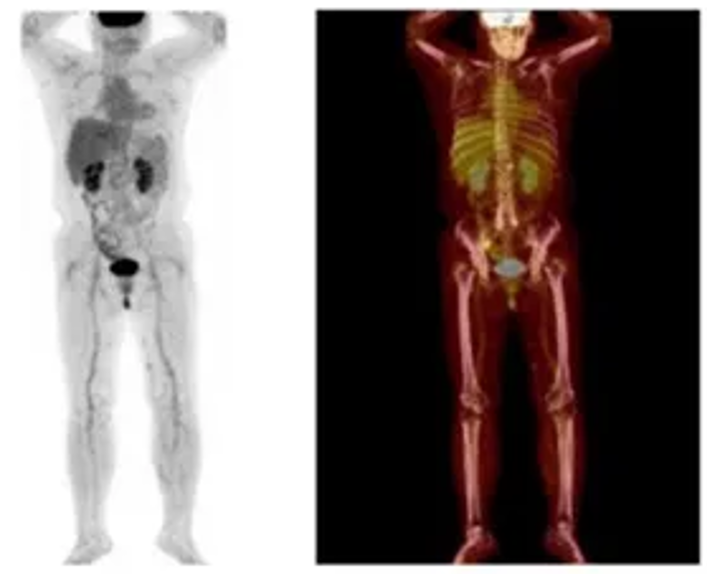

患者为32岁有生育需求女性,因“发现左侧扁桃体肿物1个月”就诊。于2024年10月进食后自觉左侧扁桃体表面出现一质软肿物,触碰易出血。颈部CT显示口咽左侧壁增厚伴左颈部淋巴结肿大。2024年11月4日于外院行左侧扁桃体及肿物切除术,病理确诊为B细胞型淋巴瘤,弥漫性大B细胞淋巴瘤。11月11日就诊于我院血液科,PET-CT检查提示左侧扁桃体术后改变伴片状FDG摄取增高(SUVmax 5.6),右侧扁桃体代谢增高(SUVmax 6.1),左颈部Ⅱ区肿大淋巴结(约20×18mm,SUVmax 17.3),符合淋巴瘤PET征象。病理显示扁桃体结构破坏,肿瘤细胞弥漫或结节样浸润,免疫组化结果为CD20(+)、PAX5(+)、CD10(30%+)、BCL6(90%+)、MUM1(80%+)、C-MYC(60%+)、BCL2(60%+)、Ki-67(80%+),符合生发中心来源的弥漫性大B细胞淋巴瘤(Hans模型),FISH检测显示BCL2与C-MYC均为阴性。血常规、血凝常规、自身抗体、生化、肝炎病毒等实验室检查及骨髓穿刺均未见异常。最终诊断为:非霍奇金淋巴瘤、弥漫大B细胞淋巴瘤(生发中心型,双表达)、IE期A组,IPI评分0分低危,aaIPI 0分低危,ECOG 0分。

图片2024-11-11 PET-CT检查提示淋巴瘤